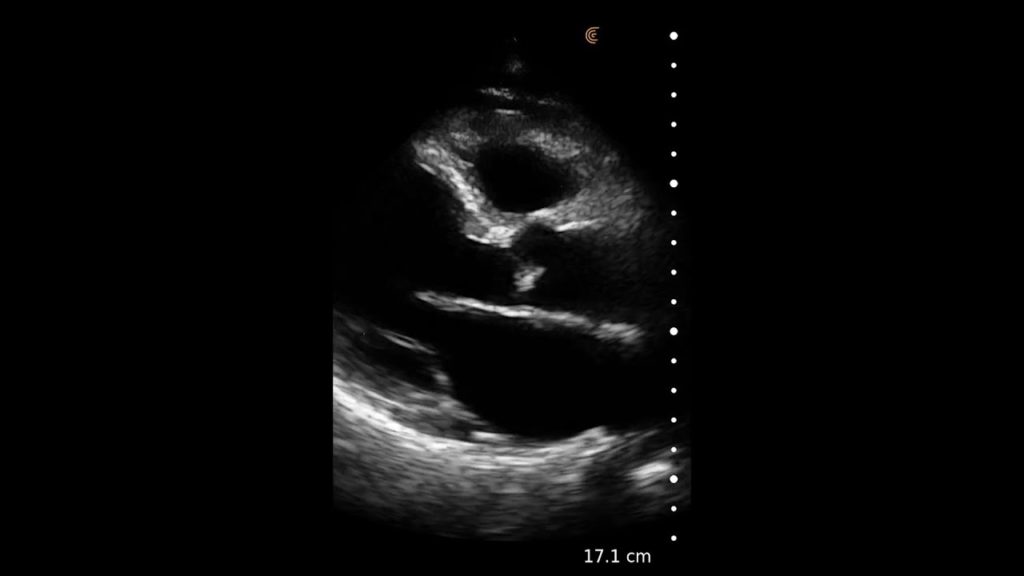

Using the jejunum as an important landmark, the hypoechoic jejunal lymph nodes can be identified. In this video Dr. Edwards explains the ultrasound appearance of normal jejunal nodes.